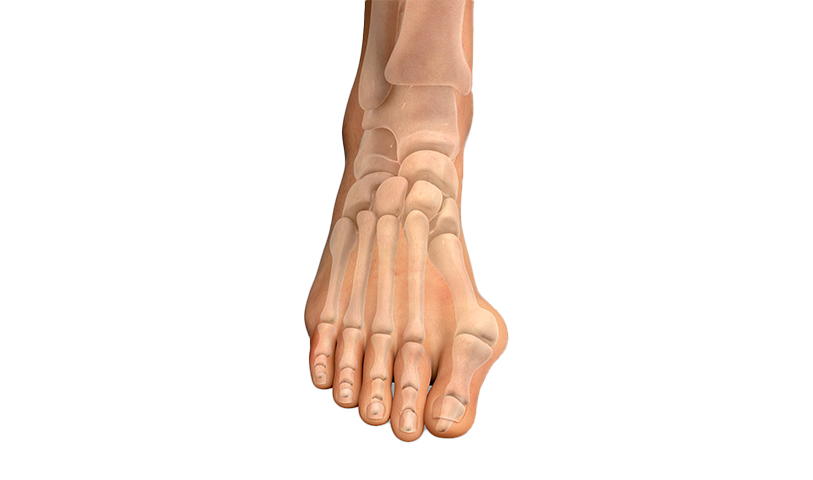

발목관절염

발은 크고 작은 26개의 뼈와 33관절로 이루어져 있는데,

발의 관절 사이 사이에 있는 연골이 손상되면서 관절에 염증성 통증과 부종이

발생하는 것을 발목 관절염 이라고 합니다.